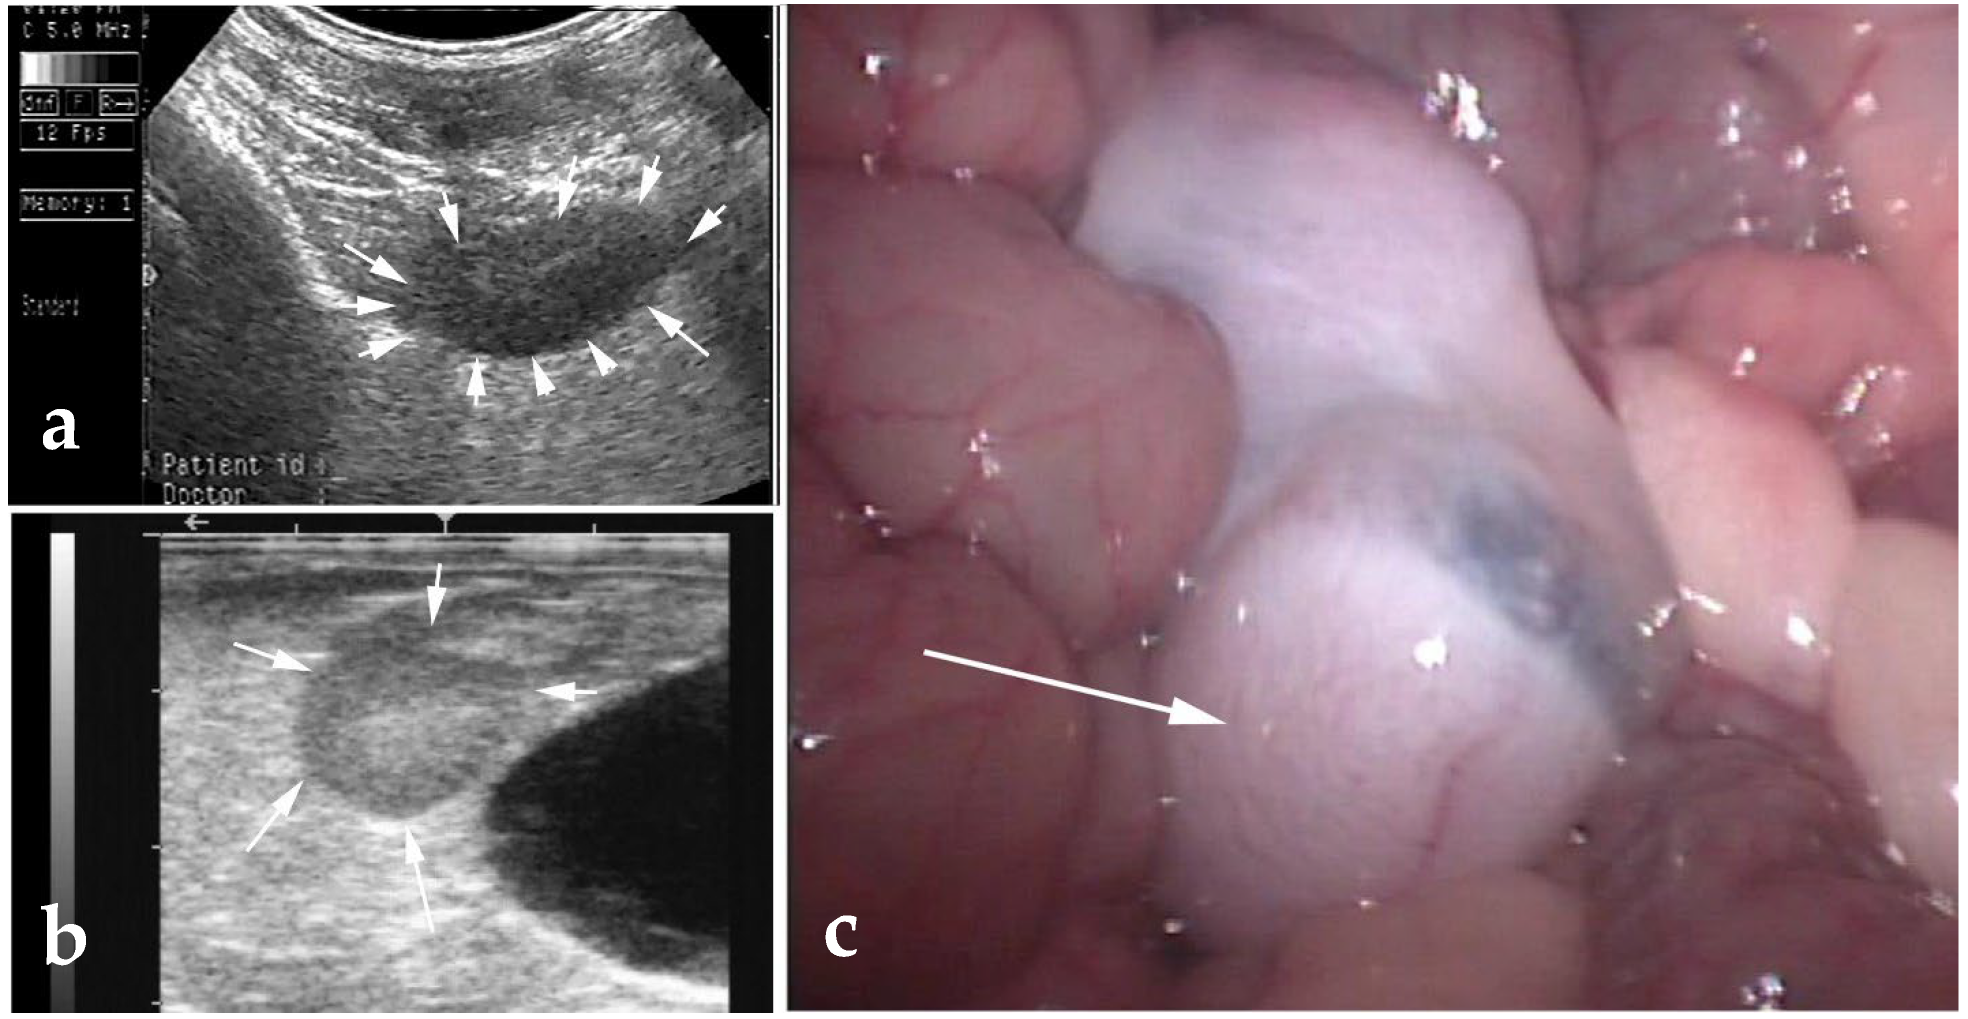

3.3. Testicular and Epididymal Cysts

- Kutzler, M.A.; Shoemaker, M.; Valentine, B.A. Bilateral Cystic Rete Testis in an Alpaca (Lama pacos). J. Vet. Diagn. Investig. 2006, 18, 303–306. [Google Scholar] [CrossRef]

- Gray, G.A.; Dascanio, J.J.; Kasimanickam, R. Bilateral Epididymal Cysts in an Alpaca Male Used for Breeding. Can. Vet. J. 2007, 48, 741–744. [Google Scholar]

- Bott, I.; Pearson, L.K.; Rodriguez, J.S. Prevalence and Pathologic Features of Rete Testis Cysts in Alpacas (Vicugna pacos). Clin. Theriogenol. 2010, 2, 395. [Google Scholar]